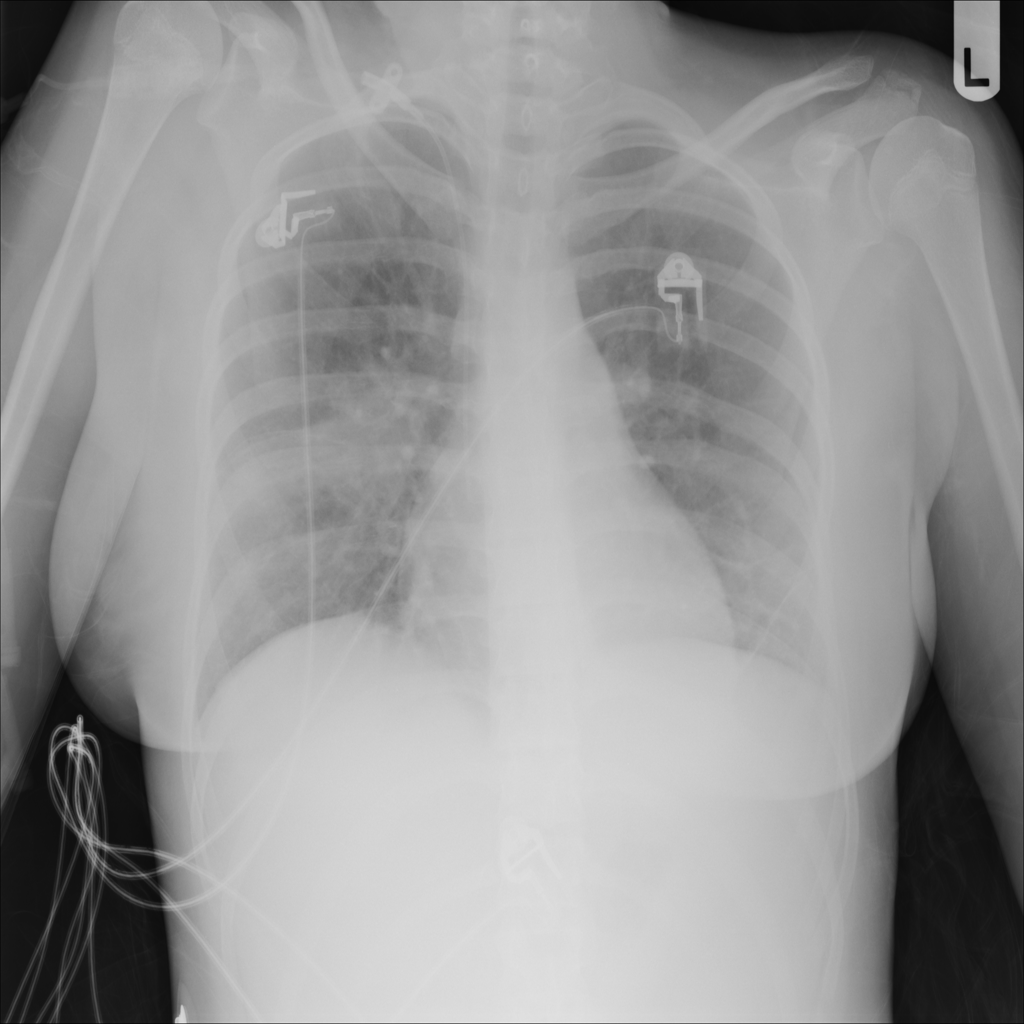

PAT-A1E2 · IMG-001Pneumonia

PAT-A1E2 · IMG-001

AP